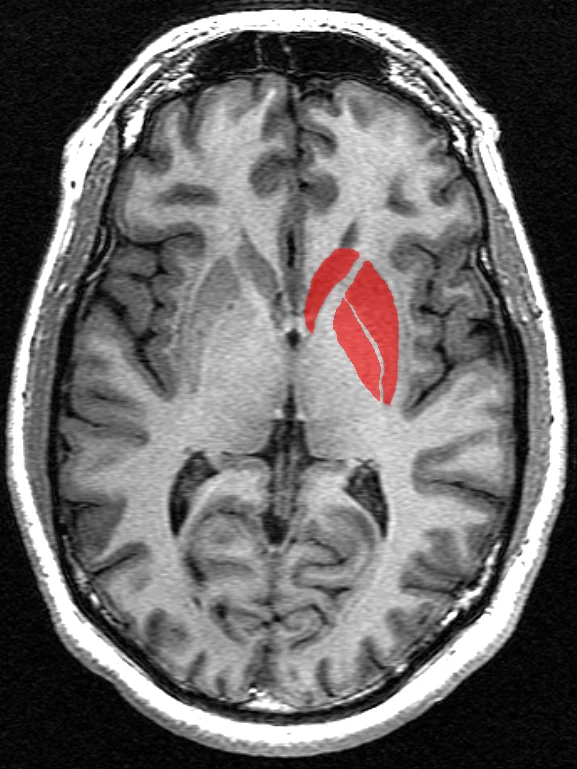

Nowe badanie wykazało, że psychopaci mają o 10 proc. większe prążkowie w mózgu niż przeciętne osoby. Sugeruje to biologiczne różnice w budowie mózgu i powiązane jest z impulsywnością i większym pragnieniem stymulacji. Występuje zarówno u kobiet, jak i mężczyzn.

Zespół neurobiologów z Nanyang Technological University (NTU Singapore), University of Pennsylvania i California State University odkrył biologiczną różnicę między psychopatami a osobami niebędącymi nimi. Wykorzystali do tego rezonans magnetyczny, aby zaobserwować, że prążkowie, czyli obszar w przedmózgowiu, było o około 10 proc. większe u osób z cechami psychopatycznymi.

Prążkowie odpowiada za motywację, podejmowanie decyzji i przetwarzanie nagród, a także pomaga koordynować działania motoryczne i odgrywa rolę w planowaniu i reagowaniu na bodźce.